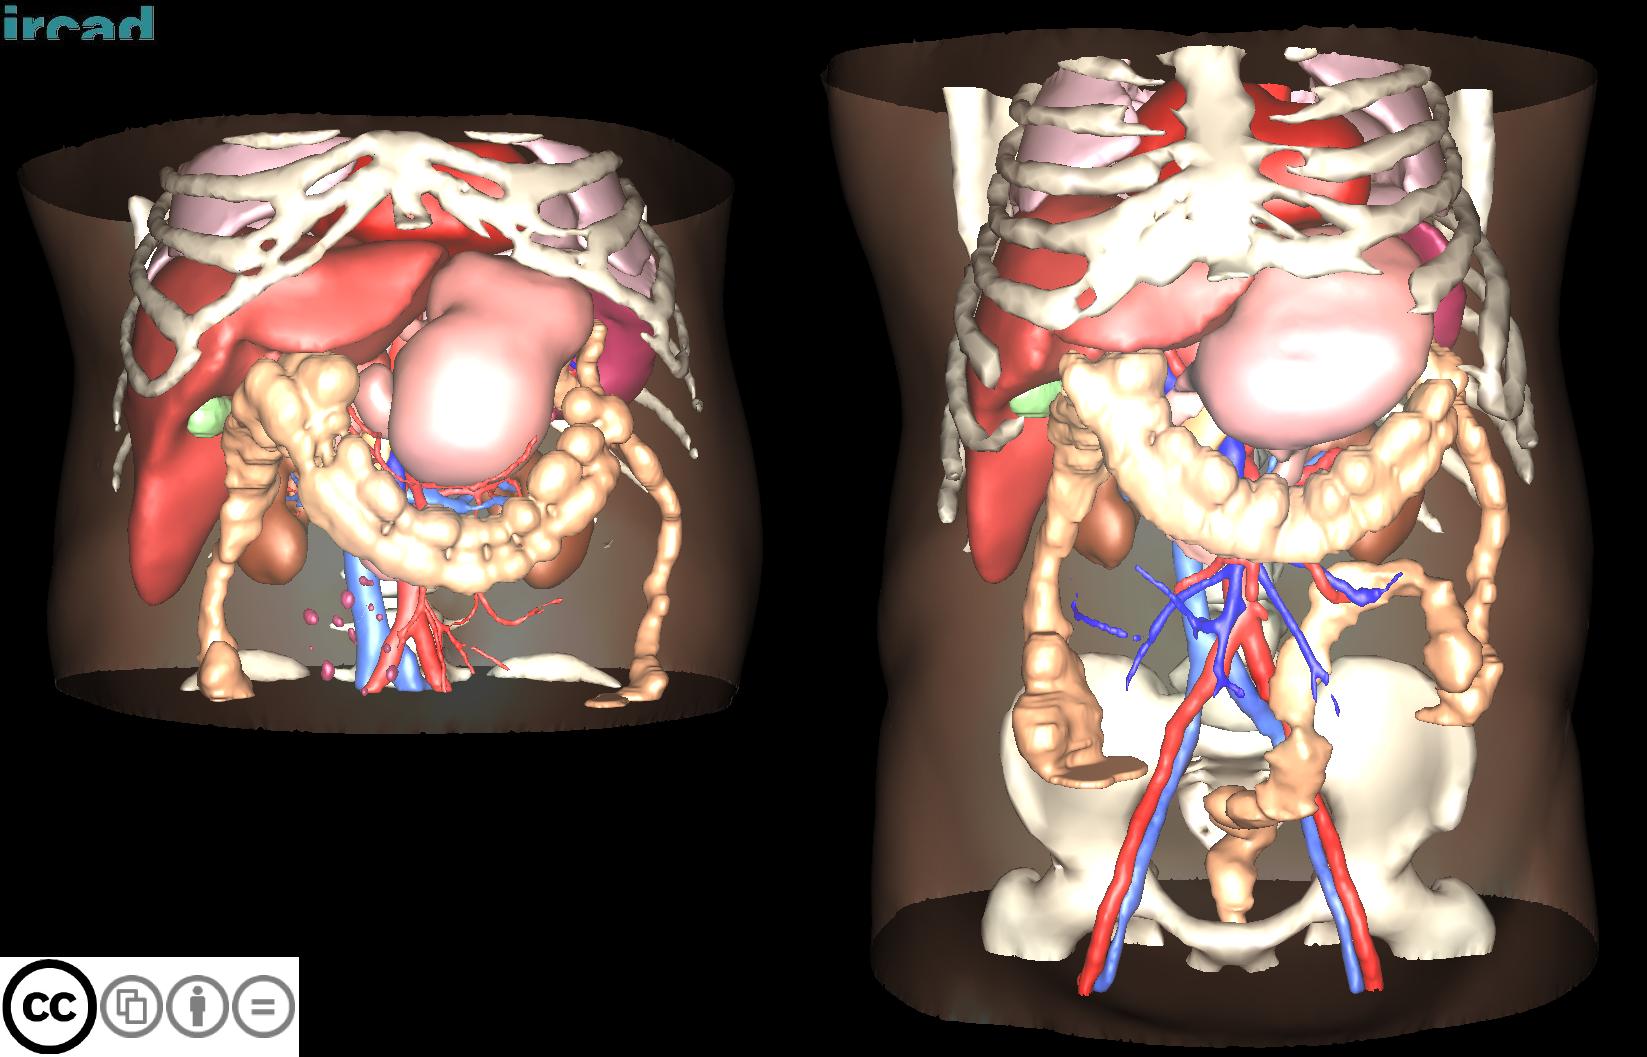

3D-IRCADB

| 名称 | 标注内容 | 类型 | 模态 | 数量 | 标签格式 | 文件格式 | License |

|---|---|---|---|---|---|---|---|

| 3D-IRCADb 01 02 | 肝脏/肝肿瘤 | 分割 | CT | 20+2 | surface mesh | dcm | CC |

3D-IRCADb是比较早的一个数据集,有两个子集,分别包含20组和2组CT片子。